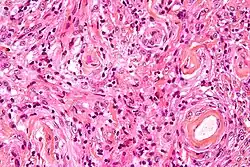

Meningioma fibroso

Este subtipo tiene aspecto mesenquimal, con una estructura en bandas y haces paralelos y entrecruzados de células fusiformes, inmersas de abundante estroma de colágeno y reticulina. Los remolinos celulares y los cuerpos de psammoma no son frecuentes.